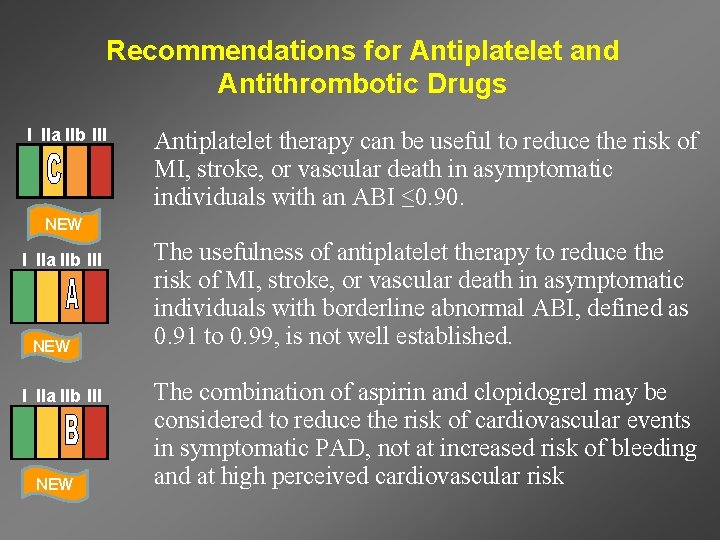

Recommendations for Antiplatelet and Antithrombotic Drugs I IIa IIb III MODIFIED Antiplatelet therapy is indicated to reduce the risk of MI, stroke, and vascular death in symptomatic PAD I IIa IIb III MODIFIED Aspirin, 75 to 325 mg, is recommended as safe and effective antiplatelet therapy. Clopidogrel (75 mg per day) is recommended as a safe and effective alternative antiplatelet therapy to aspirin

Recommendations for Antiplatelet and Antithrombotic Drugs I IIa IIb III Antiplatelet therapy can be useful to reduce the risk of MI, stroke, or vascular death in asymptomatic individuals with an ABI ≤ 0. 90. NEW I IIa IIb III NEW The usefulness of antiplatelet therapy to reduce the risk of MI, stroke, or vascular death in asymptomatic individuals with borderline abnormal ABI, defined as 0. 91 to 0. 99, is not well established. The combination of aspirin and clopidogrel may be considered to reduce the risk of cardiovascular events in symptomatic PAD, not at increased risk of bleeding and at high perceived cardiovascular risk